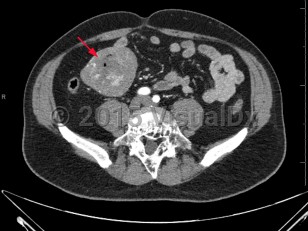

Gastrointestinal stromal tumors (GISTs) are subepithelial neoplasms most often located in the stomach (60%-70% of cases) and proximal small intestine (20%-30% of cases), but they can occur at any portion of the alimentary tract including the omentum, mesentery, and peritoneum. GISTs most commonly occur in middle-aged and older individuals, although there are pediatric forms associated with syndromes such as the Carney triad, Carney-Stratakis syndrome, and neurofibromatosis type 1.

Clinical manifestations include nonspecific symptoms such as early satiety and bloating. Often, GISTs are discovered on imaging performed for another purpose. GISTs may remain asymptomatic unless they ulcerate, bleed, or grow large enough to cause mechanical obstruction. Sites of metastases include the liver and peritoneum; lymph node metastases are not common.